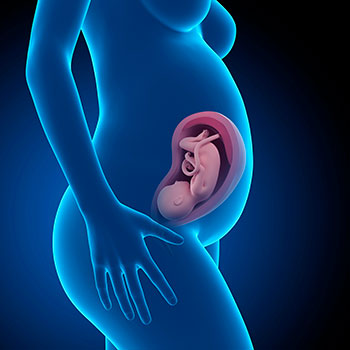

Na 31ª semana de gravide, o comprimento do teu bebé é de cerca de 40 centímetros e pesa, mais ou menos, 1,5 kilos.

A sua epiderme está mais roliça e rosada porque já tem um pouco de gordura sob a pele, e os capilares já não são visíveis à superfície.

O seu progressivo crescimento pode fazer com que se sinta um pouco apertado dentro da barriga da mamã!

Grávida de 31 semanas

Os seus olhos e ouvidos tornam-se mais aguçados e o funcionamento dos pulmões também melhora.

Idade do feto: 29 semanas.